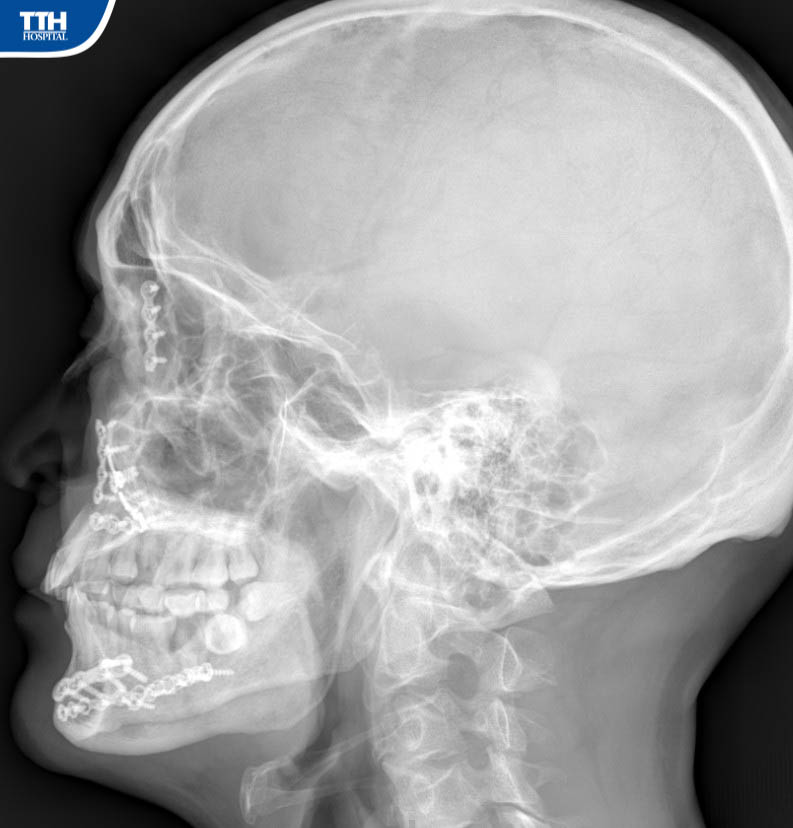

Vừa qua, Bệnh viện Đa khoa TTH Hà Tĩnh tiếp nhận bệnh nhân H.Đ.H (47 tuổi, Hương Khê, Hà Tĩnh), bệnh nhân cho biết lý do nhập viện khoa Răng Hàm Mặt là vì: ‘‘Cách đây 15 tháng đã đến Bệnh viện Hữu Nghị Việt Đức mổ kết hợp xương vùng hàm mặt, trước khi ra viện các Bác sĩ phẫu thuật nói: khi nào tháo nẹp vít thì ra Hà Nội tháo chứ tuyến dưới không tháo được". Đã đến kỳ hạn tháo nẹp vít kết hợp xương, qua tìm hiểu và được người nhà giới thiệu nên tôi quyết định đến Bệnh viện Đa khoa TTH Hà Tĩnh để tháo’’.

Theo BSCKI Trần Đức Hải – Khoa Răng Hàm Mặt Bệnh viện Đa khoa TTH Hà Tĩnh cho biết: ‘‘Ca phẫu thuật tháo phương tiện kết hợp xương phức tạp, gãy cả xương hàm trên trái và gãy xương hàm dưới 2 bên đòi hỏi kíp phẫu thuật có trình độ chuyên môn sâu về lĩnh vực hàm mặt, bởi gần như các đường rạch đều được dấu kín bằng đường trong miệng để tránh tạo sẹo ngoài da ’’.

‘‘Ca phẫu thuật diễn ra thuận lợi trong khoảng gần 90 phút. Sau phẫu thuật tháo phương tiện kết hợp xương hàm mặt, người bệnh hồi phục nhanh, từ ngày thứ 2 sau mổ. Sau 3 ngày, người bệnh có thể đi lại, sinh hoạt và xuất viện’’. Bs Hải cho biết thêm.